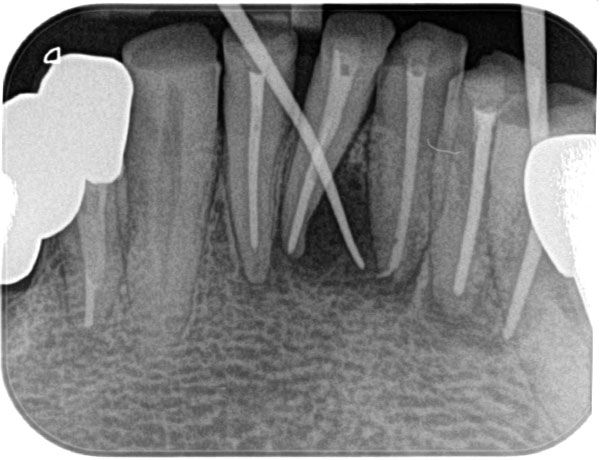

主訴: 噛むと痛い、左で食べれない。他の病院で神経が見つからない。根の先に病気がある。

通常だと手立てがなく、抜歯しかない歯も外科(根尖切除術)で治すことができます。

歯茎が腫れ、CT上では骨が大きくないことがわかります